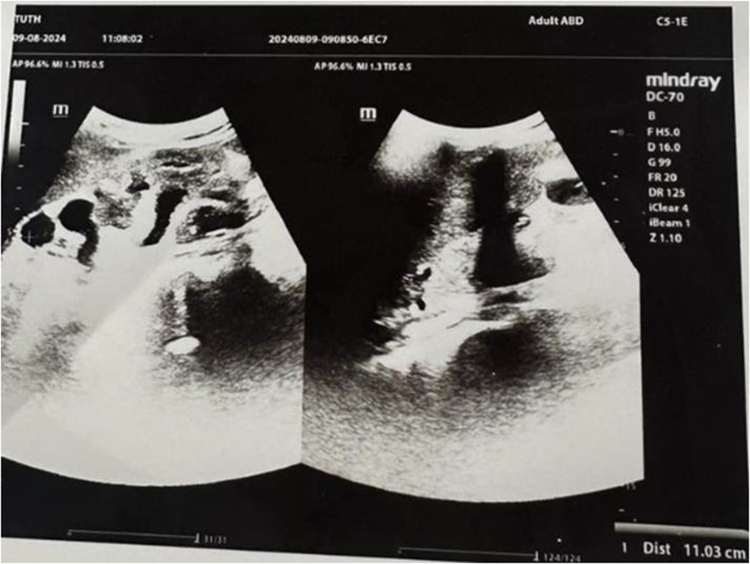

Case presentation: An 18-year-old female with stage V chronic kidney disease developed abdominal distension and bowel obstruction caused by a large renal cyst. Imaging confirmed the diagnosis, and conservative management with fluid control, dialysis, and infection management was initiated.

Discussion: The presentation of a renal cyst causing bowel obstruction is extremely rare, and the optimal management approach remains unclear. Diagnosis relies on imaging modalities such as ultrasound and CT, which help identify cyst characteristics and associated complications. In such cases, conservative treatment is generally preferred, focusing on symptom management through dietary modifications, while surgical intervention is considered only if symptoms persist despite medical therapy.